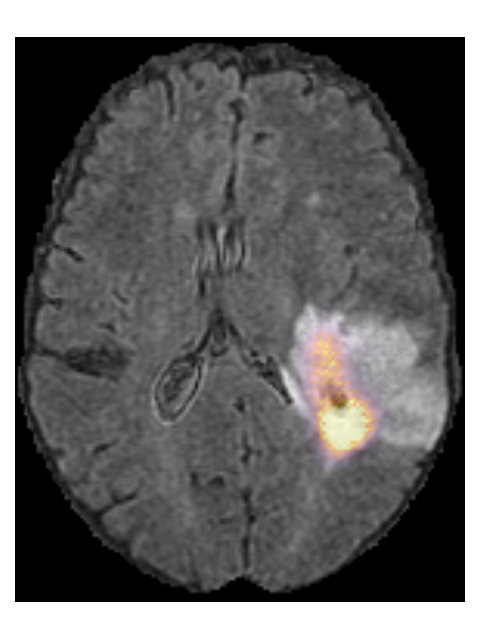

To provide insight into the behavior of our model we created saliency maps, which show which parts of the scans contributed the most to the prediction. These saliency maps are shown in Figure 6 for two example patients from the test set. It can be seen that for the LGG the network focused on a bright rim in the T2w-FLAIR scan, whereas for the HGG it focused on the enhancement in the post-contrast T1w scan. To aid further interpretation, we provide visualizations of selected filter outputs in the network in Appendix D, which also show that the network focuses on the tumor, and these filters seem to recognize specific imaging features such as the contrast enhancement and T2w-FLAIR brightness.